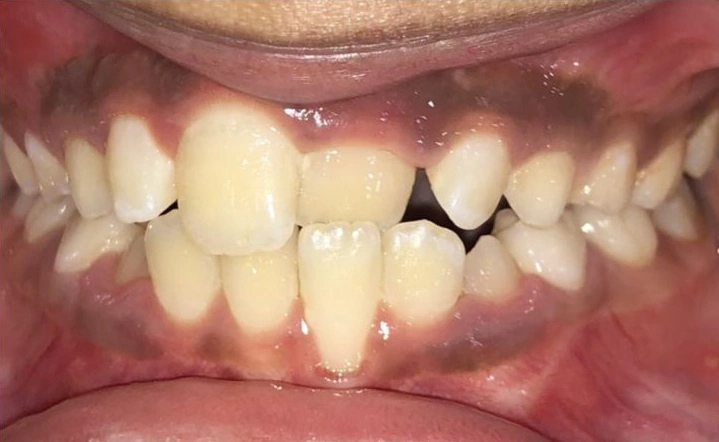

2. The Underbite: When the Upper Teeth Are Behind the Lower Teeth

Another common issue is an underbite. This is a horizontal problem where the lower teeth are pushed out past the upper teeth.

It can lead to functional problems and damage if not addressed early.

Visual Example:

Example #1 (young adult):

Example #2 (young adult):